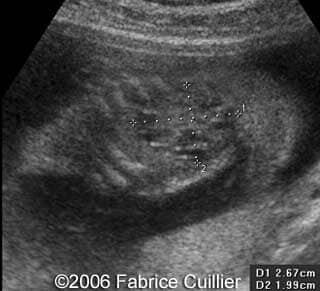

• an abnormal polycystic left kidney (34 X 17 mm) with an abnormal corticomedullar differentiation. This kidney was on the lumbar fossa.

At 24 and 26 weeks, the left kidney lesion had increased. At 34 and 37 weeks, the anomalies were the same. The baby was delivered vaginally (male, 3000 g). At day five, the kidney abnormalities were confirmed. Nevertheless the creatinine level was normal. One month later, a scan revealed a normal right kidney (50 mm) and a left kidney with cysts. The creatinine level was in the normal range. The child was operated (left nephrectomy). The diagnosis of multicystic kidney disease was confirmed.